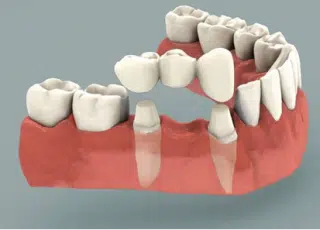

Coronas Dentales y Puentes

Una corona dental, también conocida como una funda, se utiliza para rehabilitar a un diente que ha sufrido daños o destrucción en las áreas visibles. Una corona es una restauración completa de 360º que se coloca sobre la estructura sana del diente.

Un puente dental a menudo se utiliza para cubrir el espacio de un diente que ya está perdido. Por ejemplo, si le falta un diente, entonces usted necesita un puente de tres piezas.